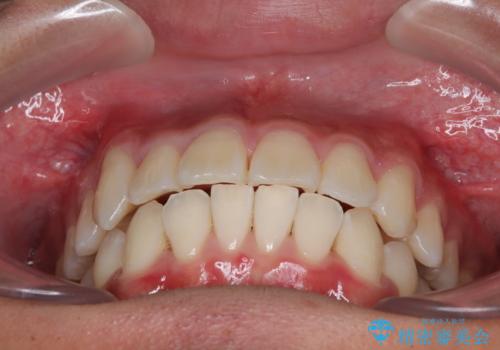

- 前歯のデコボコと右上の八重歯を気にして来院された患者様です。

マウスピース矯正とワイヤー矯正で悩んでいらっしゃいましたが、非常に強い咬合力であることや、お仕事柄不規則な生活リズムになることが多いとのことで、ワイヤー装置にて矯正治療を行うこととしました。

1年強でワイヤー装置を外すことができ、思ったよりも短期間で終了したため、患者様には大変喜んでいただきました。